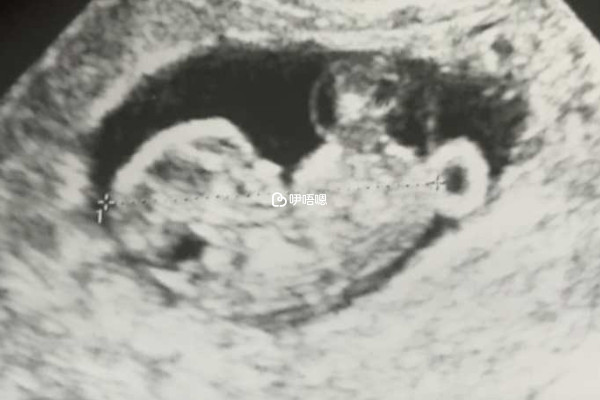

眾所周知,一個完整的妊娠是受精卵形成,然後在子宮腔內進行著床,之後胚胎進一步生長髮育的過程,但是生化妊娠就是並未達到著床的地步,也沒有完整的妊娠發生,臨床上,導致生化妊娠最常見的原因是受精卵本身有缺陷、卵巢黃體功能不足、子宮內膜異常、子宮發育不良,或者是患有子宮肌瘤,一般來說,無論是哪一種原因導致生化妊娠並不能排除不孕不育,即:

對於生化妊娠後的女性來說,若是能夠自然受孕的話,一定要在確保沒有異常之後再備孕,若是無法自然受孕的女性,則可以選擇試管嬰兒技術進行助孕。